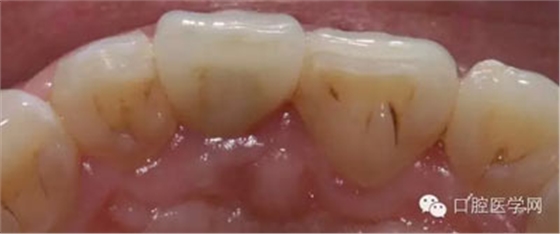

2、拆除烤瓷冠,牙體制備及11 3Mz350樹脂修復(fù)

3、由北京精藝義齒工作室高級(jí)技師靳曉輝老師制作的全瓷冠